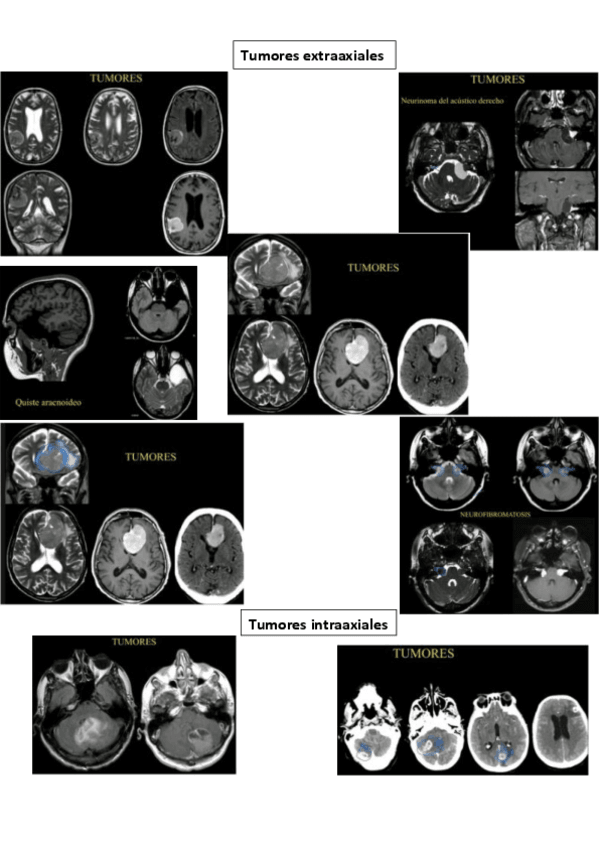

Practicas-SNC-II-Tumores-Infeccion.pdf